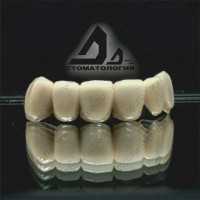

Протезирование зубов

| Установка коронки на зуб | от 5 000 ₽ до 40 000 ₽ |